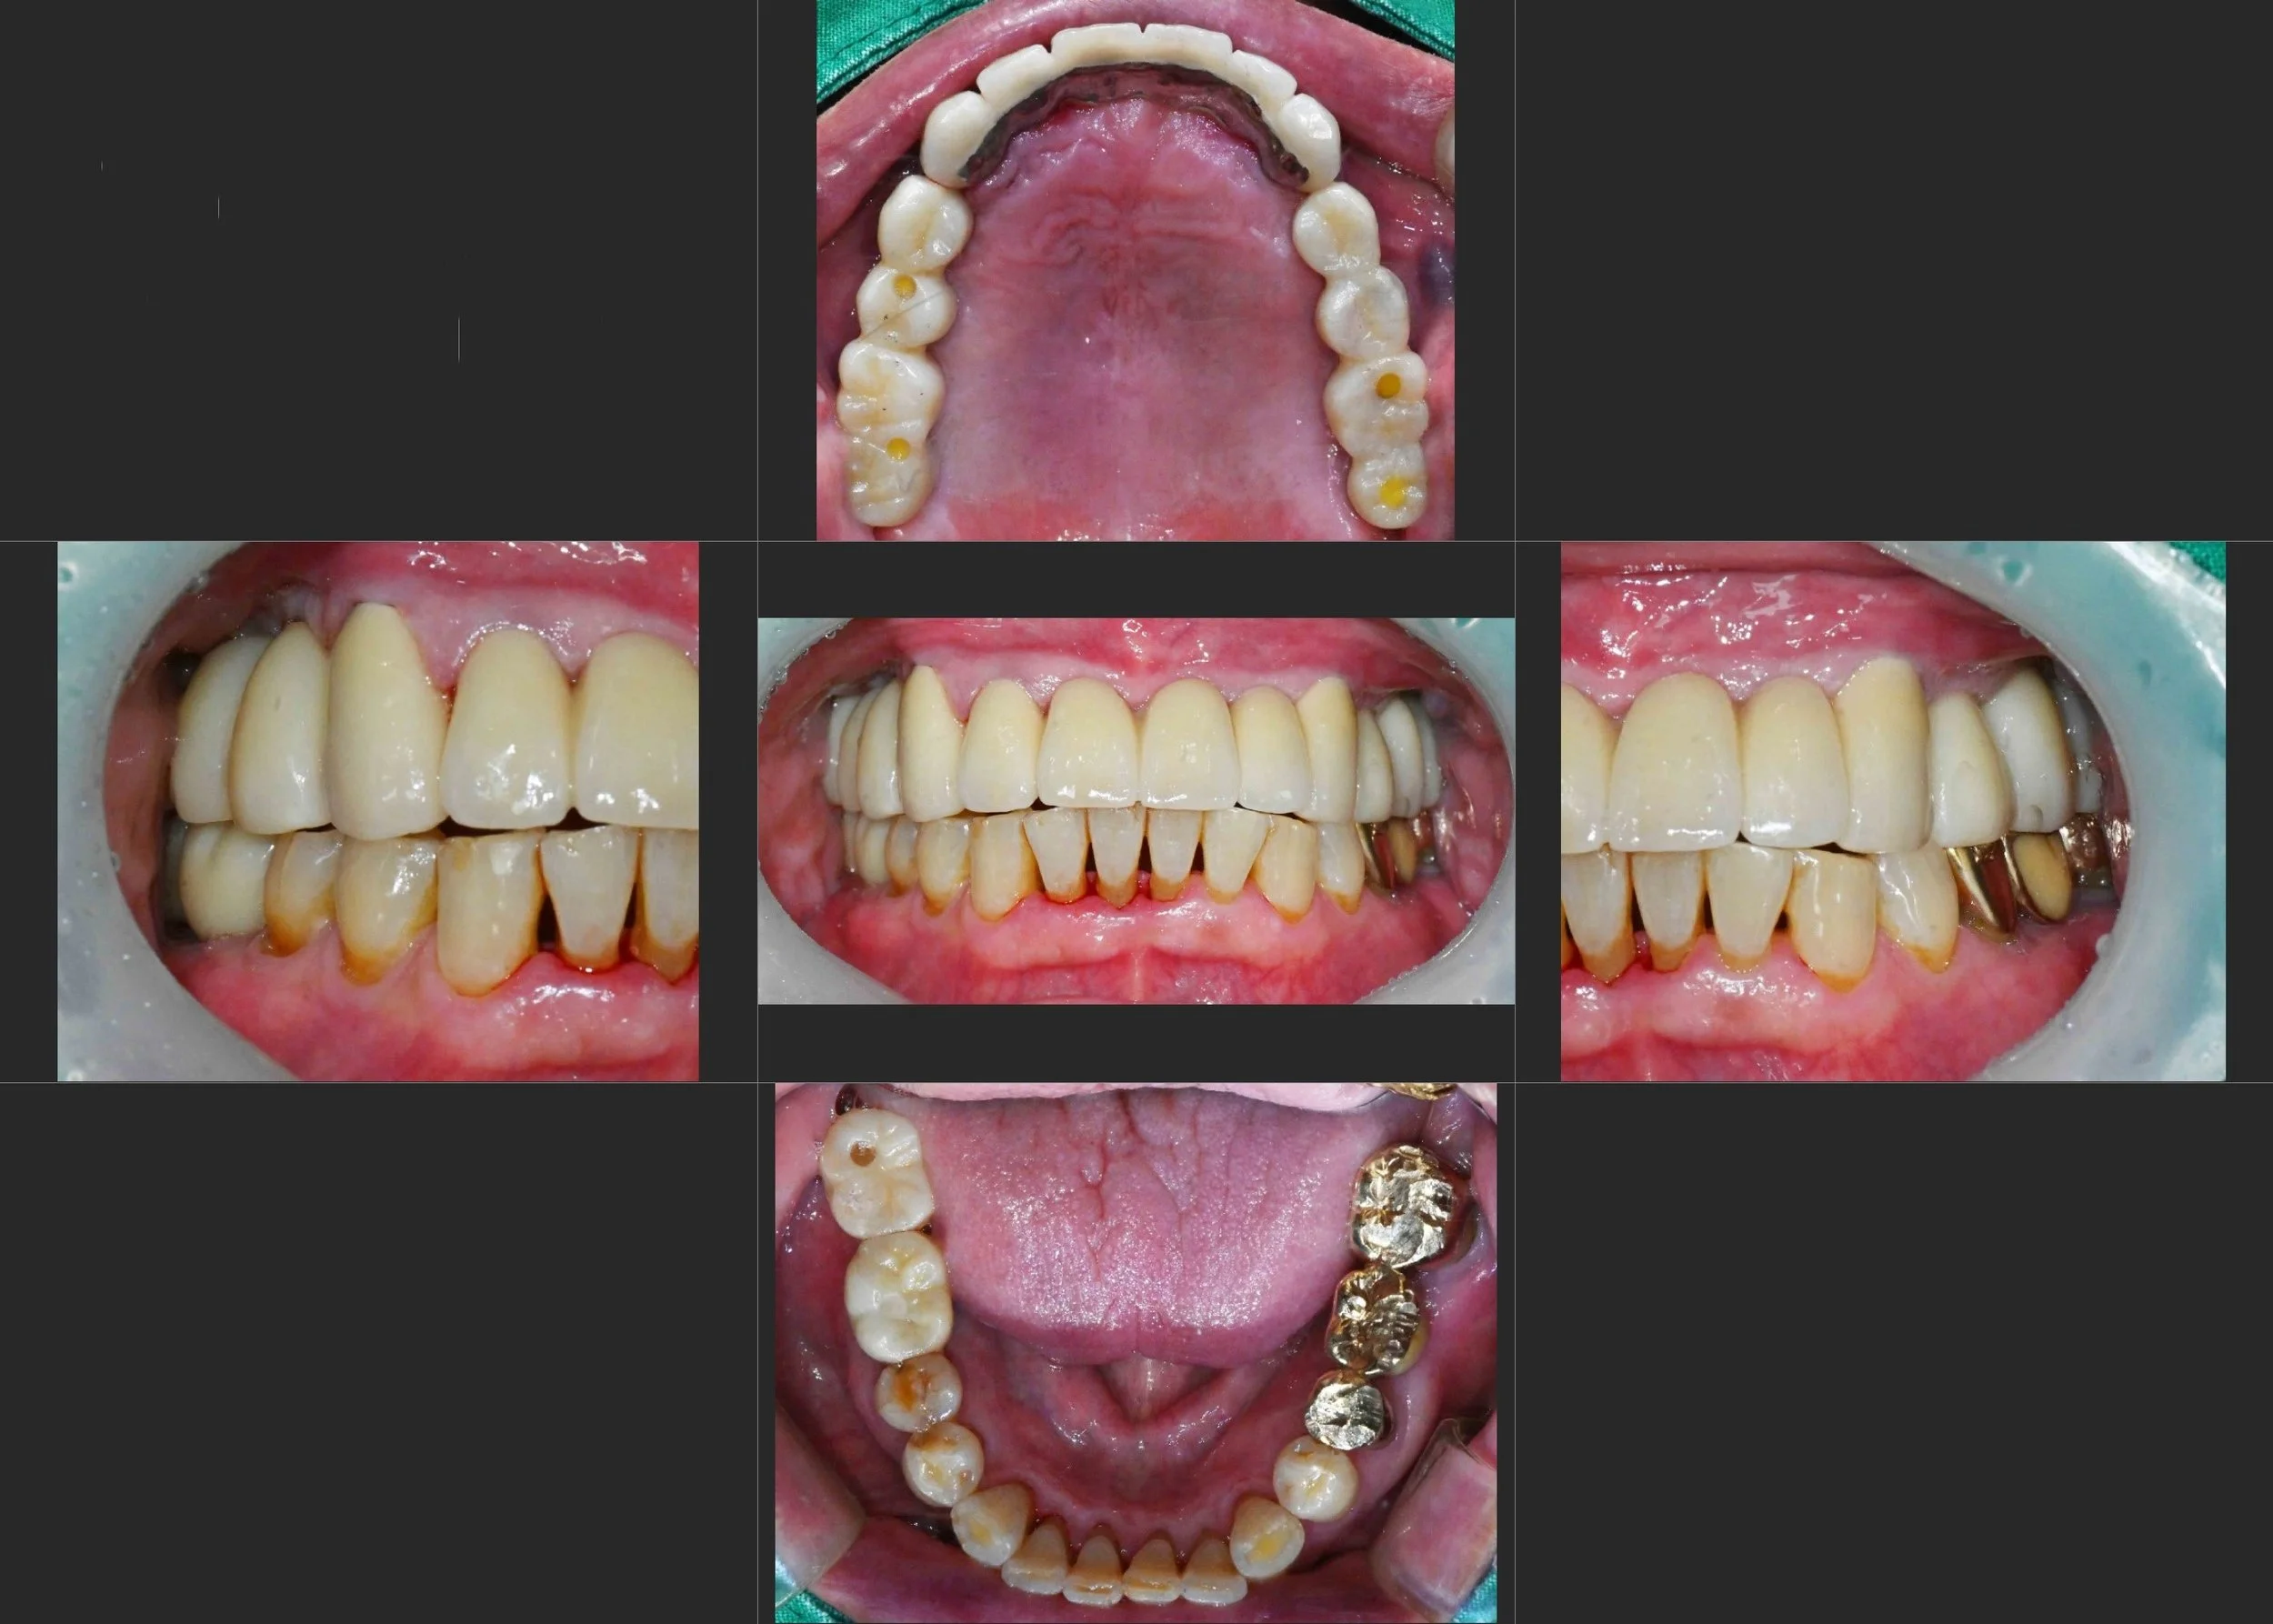

OPG - BEFORE

The primary clinical findings included:

• Posterior Bite Collapse: Loss of posterior support resulting in a reduced Vertical Dimension of Occlusion (VDO).

• Pathological Anterior Flaring: Without posterior stops, excessive forces caused the maxillary anterior teeth to drift labially (flaring), creating aesthetic and functional distress.

• Failing Prosthetics & Periodontitis: Existing restorations were ill-fitting, and generalized periodontal disease had further destabilized the remaining teeth.